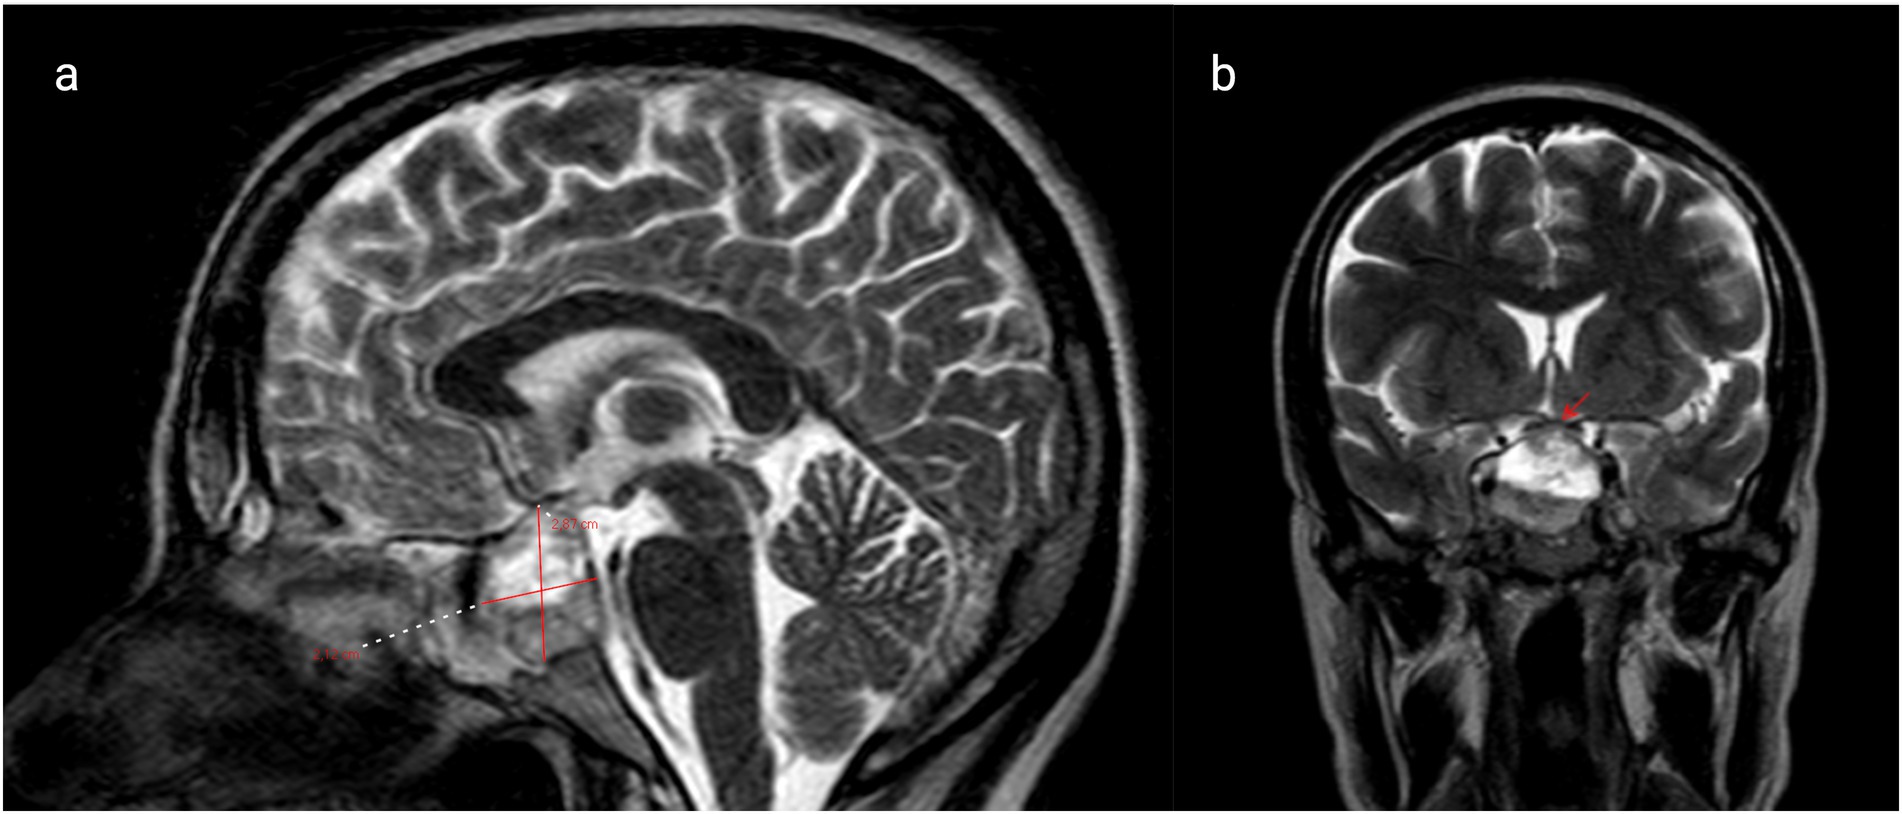

Background: Prolactinomas are the most common functional pituitary adenomas and may lead to infertility, visual field defects, and neurological impairment. Pregnancy poses unique challenges in women with macroprolactinomas due to the potential for tumor enlargement under the influence of gestational hormonal changes. Case: We present the case of a 40-year-old woman who conceived through in vitro fertilization (IVF) and presented at 38 + 3 weeks of gestation with new-onset diplopia. Magnetic Resonance Imaging (MRI) revealed a 29 mm hemorrhagic macroprolactinoma causing compression of the optic chiasm. The tumor had been previously asymptomatic and untreated. Management was undertaken by a multidisciplinary team including obstetricians, endocrinologists, neurosurgeons, and anesthesiologists. An elective caesarean section was performed under general anesthesia with careful attention to intracranial pressure control and hemodynamic stability. Outcome: Delivery was uneventful, with no perioperative neurological or anesthetic complications. The patient was discharged in good general condition and commenced on long-term dopamine agonist therapy, with planned close endocrinological and neurosurgical follow-up. Conclusion: This case highlights the importance of early diagnosis, individualized management, and multidisciplinary coordination in pregnant women with macroprolactinomas. Dopamine agonists remain the cornerstone of therapy and are generally safe during early pregnancy. Meticulous anesthetic planning is essential to optimize maternal and fetal outcomes.